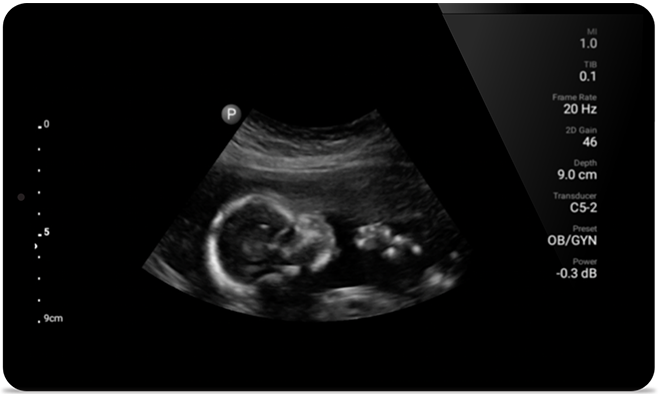

Congestive heart failure is a growing issue today. Discovering it earlier with in-office ultrasound can greatly improve survival rates.

• 5 to 2 MHz extended operating frequency range • 50mm radius of curvature • 2D, color Doppler, M-mode, advanced XRES and multivariate harmonic imaging, SonoCT • High-resolution imaging for deeper applications: abdominal, gall bladder, OB/GYN and lung imaging preset optimizations • Center line marker • USB-C transducer with replaceable cable